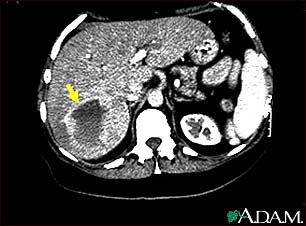

Hemangioma - CT scan

This upper abdominal CT scan shows a blood vessel tumor (hemangioma) in the liver.